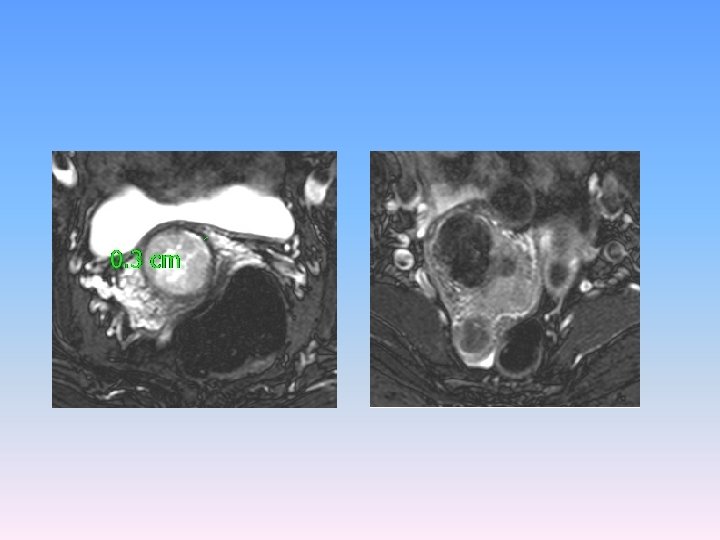

MRI V oblasti cervixu expanzivní útvar 3 cm v průměru s odlišným signálem oproti okolní děloze a vlastním myomům, expanze má vyšší obsah vody. Zaujímá celý vnitřní prostor cervixu, podél expanze zůstává tenký lem tkáně šíře 3 mm. Nikde nepřechází expanze z cervixu na okolní struktury.

Děložní tělo, parametria a poševní manžeta bez nádorové infiltrace Téměř celé děložní hrdlo infiltrované strukturami Karcinosarkomu (M 8990/32), kdy přibližně z poloviny je novotvar tvořen strukturami sarkomovými, z poloviny strukturami méně diferencovaného endometroidního adenokarcinomu. Intaktní tkáň na povrchu cervixu šíře 3 mm. Invaze do krevních ani lymfatických cév nezastižena. Omentum, appendix, pánevní a paraaortální lymfatické uzliny (36) bez maligní infiltrace